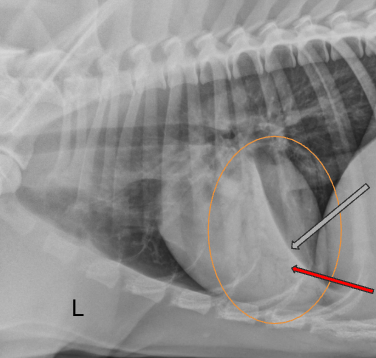

Label the image

intra-capsular soft tissue swelling

osteophytes

enthesophytes

subchondral erosions

intra-articular calcified bodies

subchondral sclerosis

subchondral cysts

joint space narrowing